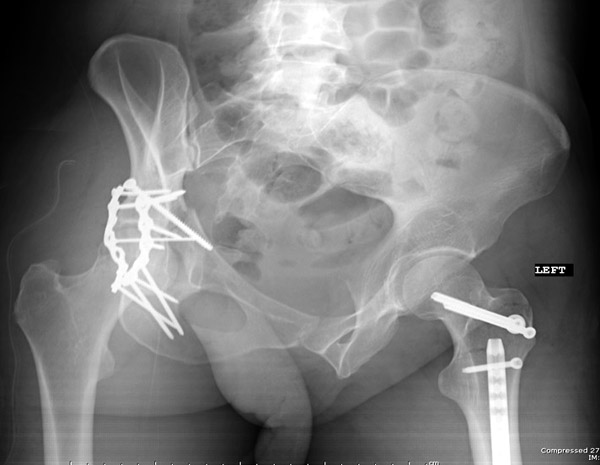

Пациент 19 лет, ДТП в сентябре 2012 г, оперирован поэтапно в др. клинике. В сентябре пациенту первым этапом была проведена операция – МОС лодыжек правой голени, МОС правой бедренной кости. Через 2 недели была проведена операция МОС костей таза и открытое устранение вывиха правого бедра.

Повторная операция – реостеосинтез костей таза была проведена через 1 месяц после первичной. Дз: задний вывих правого бедра (сроки -3 месяца). Асептический некроз головки правой бедренной кости. Неконсолидирующийся перелом средней трети правой бедренной кости, неправильно консолидирующийся перелом лодыжек правой голени с подвывихом стопы кзади, передняя медиальная нестабильность правого К/С. Сгибательно-приводящая контрактура правого Т/Б сустава, сгибательно-разгибательная контрактура правого К/С, эквинусная установка в правой стопе на фоне пост-операционного пареза

Перелом вертлужной впадины отличается от “переломов таза” не только исследованием, но также тактикой. По классификации Летурнеля расположение линии перелома характерно для поперечного перелома вертлужной впадины, но наличие шурупов в заднем крае (второй снимок) и вывих бедра подтверждают, что здесь сочетание заднего края с поперечным переломом.

Через задний доступ смогли сделать частичную репозицию, а здесь напрашивался двойной доступ спереди и сзади. Репозиция в положении на боку затруднительна, и вытяжение за перекладину над операционным столом облегчило бы репозицию.

Здесь пара случаев, где обычный поперечный перелом зафиксирован задним доступом и второй поперечный перелом в сочетании задней стенки, где на КТ слева в шейке обнаружен перелом без смещения, который зафиксирован профилактически.